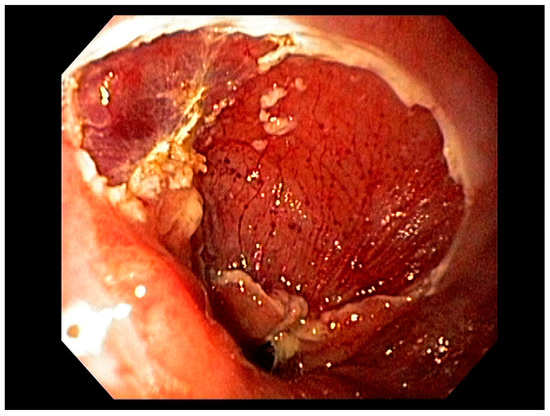

Early endoscopic detection of premalignant lesions such as Barrett’s esophagus, gastric intestinal metaplasia, and mucosal cancer using optical chromoendoscopy techniques such as narrow-band imaging (NBI) combined with high-definition white light imaging (HD-WLE) is becoming routine across the world. Targeted biopsies from endoscopically suspicious areas or using the updated Sydney protocol are important for successful diagnosis [15][16]. In the presence of dysplasia with visible lesions or carcinoma, endoscopic ultrasound (EUS), a minimally invasive procedure, has a well-established role in the early diagnosis and locoregional staging of non-metastatic foregut malignancies [17][18][19], see Figure 2.

Figure 2. Barrett’s esophagus with nodules under narrow band imaging (NBI) (arrows).

Factors including lesion size, histological features, anatomical stage, and esophageal location are important variables for determining favorability of endoscopic therapy, demonstrating curative resection in some studies [20]. Adenocarcinoma of the esophagus, limited to the mucosa (T1a)—see Figure 3—is amenable to endoscopic resection, with excellent long-term outcomes. Other tumors such as neuroendocrine tumors of the foregut may also be amenable to endoscopic therapy, including endoscopic mucosal resection (EMR) or endoscopic submucosal dissection (ESD). Specifically, these therapeutic approaches are used for resection of mucosal-based lesions, depending on the size, location, submucosal involvement, and complexity.

Figure 3. T1a esophageal cancer in Barrett’s Esophagus.